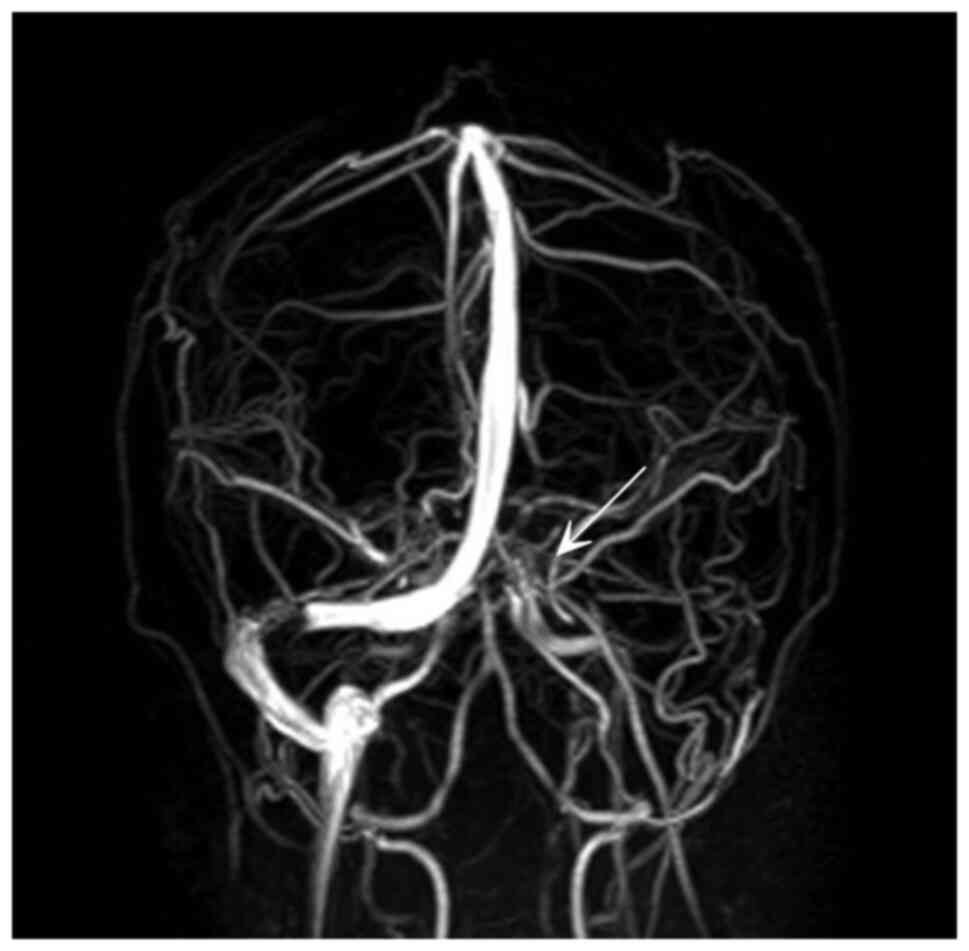

Figure 3

Magnetic resonance venography illustrating the absence of flow in the straight sinus and bilateral transverse sinuses (white arrow).

A computed tomography (CT) scan of the head revealed an abnormal hyperattenuation in the straight sinus and bilateral transverse sinuses (Figs. 1 and 2). A diagnosis of CSVT was made following a consultation with a neurologist. The patient was treated with enoxaparin at 6,000 IU, levetiracetam at 1,000 mg and mannitol at 100 ml via an intravenous drip. Following admission, a magnetic resonance venography revealed the absence of flow in the straight sinus and bilateral transverse sinuses (Fig. 3). A thrombophilic investigation revealed a plasma homocysteine level of 59.03 µmol/l (upper normal limit, 15.39 µmol/l) and a vitamin B12 level of <148 (lower normal limit, 187 pg/ml). The levels of protein C (70-140%), protein S (60-130%) and antithrombin III (75-125%) were within the normal range. CSVT secondary to homocystinemia was diagnosed, which is an unusual, yet treatable condition.